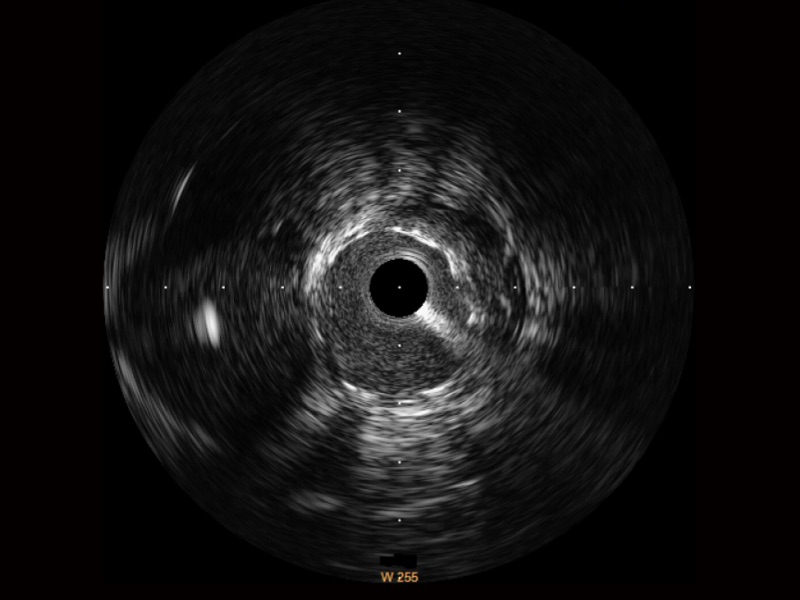

传统IVUS图像

对比传统IVUS导管成像,哈哈体育官网宽频IVUS图像的近场支架梁显影更细腻,远场中膜外血管仍清晰可辨,兼顾远中近,兼顾分辨力与穿透深度